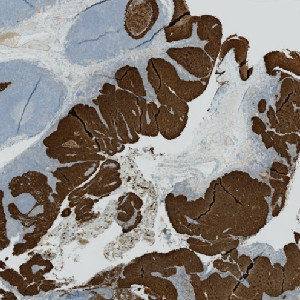

Figure 2

The serial PHH3 stained slide.